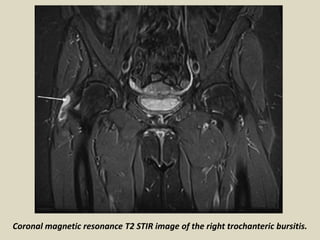

Trochanteric bursa

Pfirrmann and colleagues describe three major bursae about the greater trochanter. The

trochanteric bursa is the largest of the three. It covers the posterior facet, deep to the gluteus

medius tendon and the proximal part of the vastus lateralis insertion. It is located beneath the

gluteus maximus muscle and the iliotibial tract. This bursa does not extend over the anterior border

of the lateral facet. It is lined by a small layer of fat on both sides. Therefore, it can be routinely

identified on nonenhanced coronal MR images as a fine linear structure paralleling the posterior

facet. Trochanteric (subgluteus maximus) bursitis is a common cause of hip pain, and is associated

with obesity, trauma, inflammatory arthritides, and in patients with total hip arthroplasty.

Coronal magnetic resonance T2 STIR image of the right trochanteric bursitis.